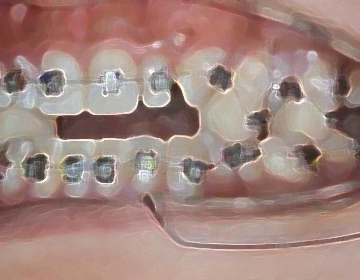

矯正治療では、歯並びを治すだけでなく、噛み合わせの改善によって3次元的顎の位置を修正し、

顎のバランスを整えることで全身のバランスを最良の状態へと導きます。

半調節性咬合器で噛み合わせ、CTで骨格のズレをチェックし治療計画を立案します。

白須賀インダイレクト法で正確に装着します。

噛み合わせを変化させ顎を3次元的に動かします、歯の噛み合わせの上に材料を盛って噛み合わせを変えます。

通常のワイヤーではできない移動はベンド(曲げる)したワイヤーでおこないます。

身体の反応を診ながら、噛み合わせ位置を微調整します。

ブラケットを除去し、リテーナー装着します。

経過を診ながら、矯正後治療が必要な歯を治療します。